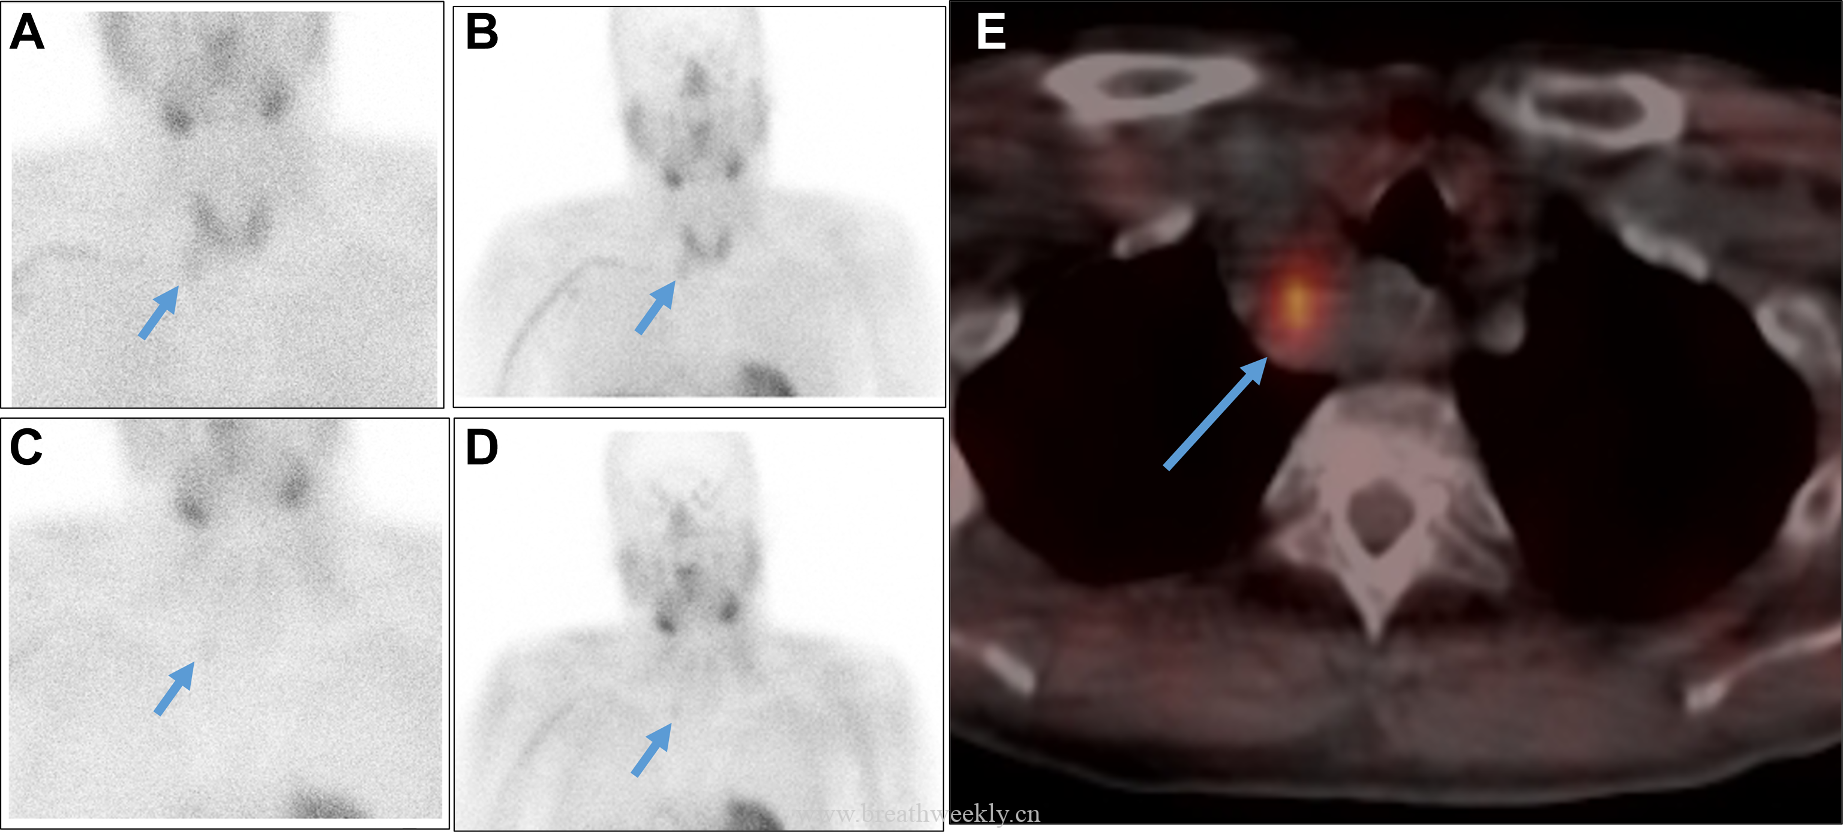

⁹ᵐTc – 甲氧基异丁基异腈甲状旁腺显像:早期及延迟图像均可见甲状腺右叶下方异常摄取灶,摄取位于右上纵隔囊性病灶的实性成分内。

临床过程:因纵隔病灶位置位于甲状腺右叶后下方,术前考虑异位胸腺瘤或异位甲状旁腺腺瘤。CT及超声示无claw sign,排除甲状腺来源。99mTc-Sestamibi显像定位病灶。MG予糖皮质激素及IV免疫球蛋白治疗效果良好;高钙血症予IV补液及cinacalcet治疗。最终行机器人辅助纵隔甲状旁腺腺瘤及胸腺切除术,病理确诊甲状旁腺腺瘤。术后患者恢复良好。